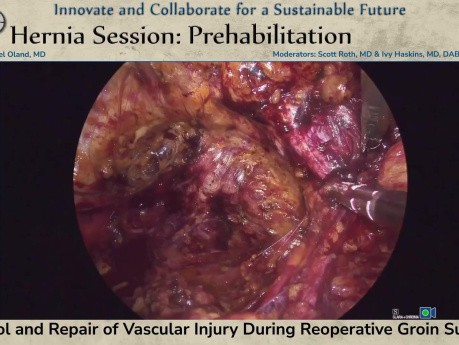

Control y reparación de lesiones vasculares durante...

El control y la reparación de lesiones vasculares durante la cirugía de reintervención inguinal fueron presentados en la sesión SS03: Hernia: Sesión de prehabilitación por el Dr. Gabriel Oland el 17 de...